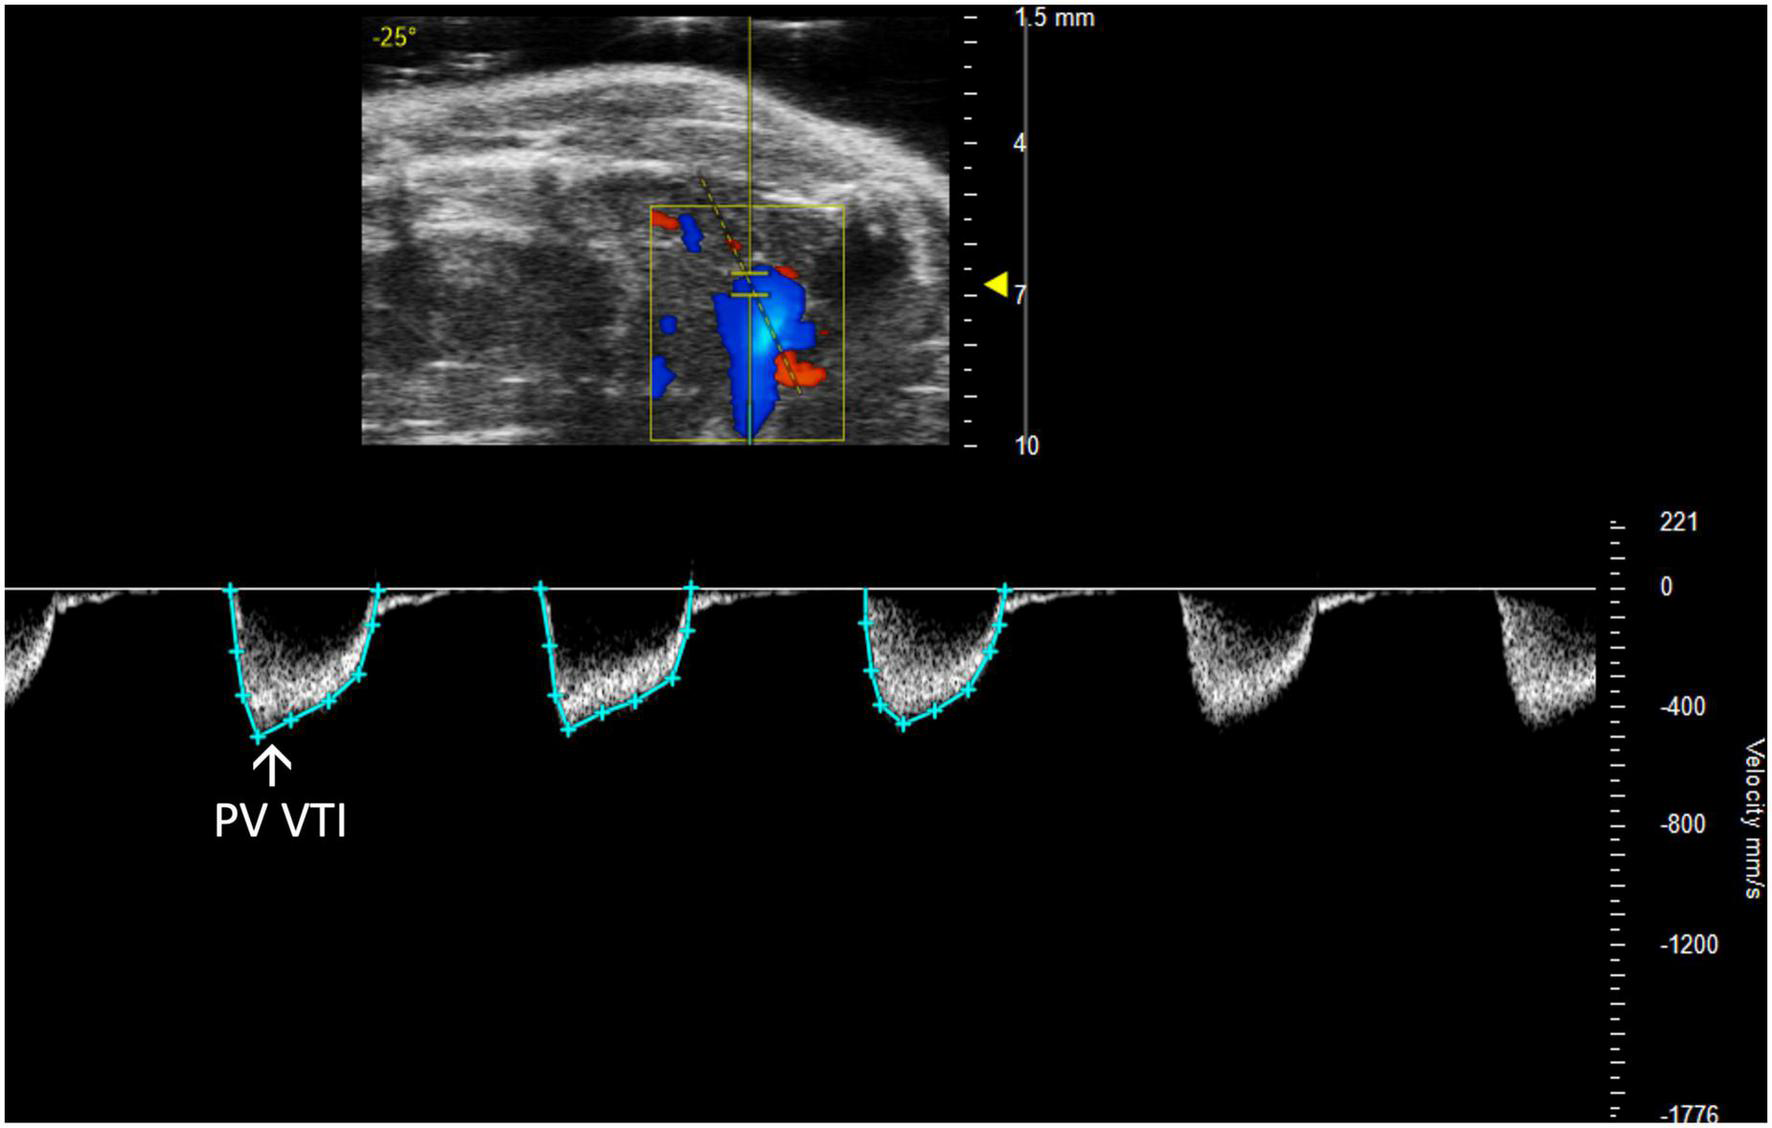

2.2.2 Pulmonary artery and valve

Pulmonary and right ventricular parameters are more informative when applied concurrently. RV dysfunction in the absence of elevated PA pressures indicates isolated RHF, while RV dysfunction concurrent with elevated PA pressures could indicate pulmonary hypertension leading to RHF or LHF leading to RHF. PA and PV measures may be incorrectly assumed to be interchangeable; however, the PA is anatomically distal to the PV in mice, and images should be captured accordingly. Measurements are made of PW Doppler mode images with the marker overlying either the PA or PV (Figures 4, 5).

FIGURE 5

The pulmonary valve velocity time integral (PV VTI), a measure of blood flow through the pulmonary valve, is calculated by measuring the area under the curve in pulsed wave (PW) Doppler mode of the parasternal long axis view (PLAX).